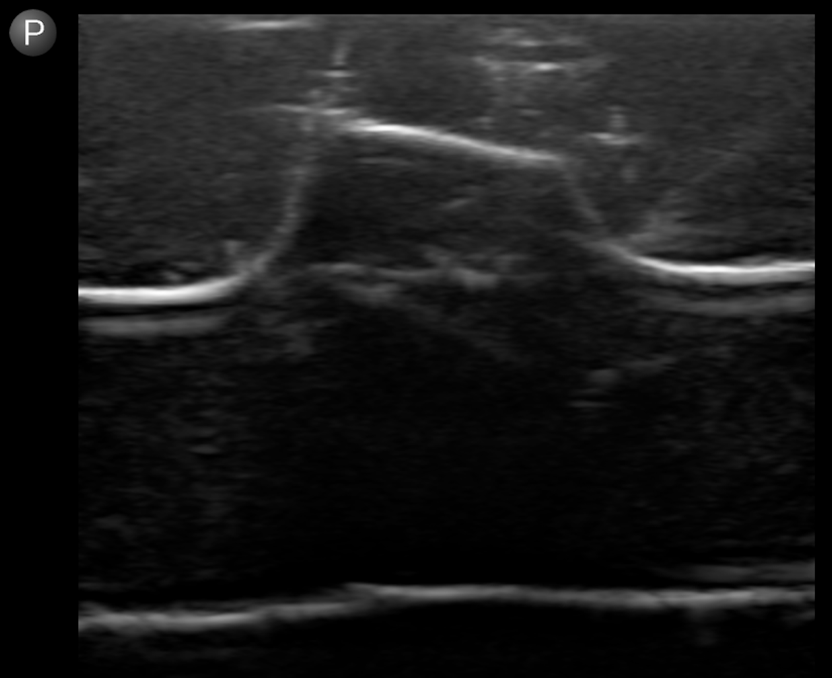

Meat models have been a popular DIY solution to train emergency medicine providers how to perform nerve blocks, as they show fascial planes, muscular anatomy, and allow for hydrodissection and injection without ruining the model. Another significant upside is that these models can be frozen and still maintain an appropriate ultrasound appearance. There are downsides, however, including that these models usually take at least a few hours to build, they spoil after some time, and while they can be injected, once the fascial plane is opened it affects the anatomy for the next user, making it potentially more difficult to identify. (Image 1 and 2)

NerveBlock-Image2 Aug2024.pngImage 2. Meat model on POCUS